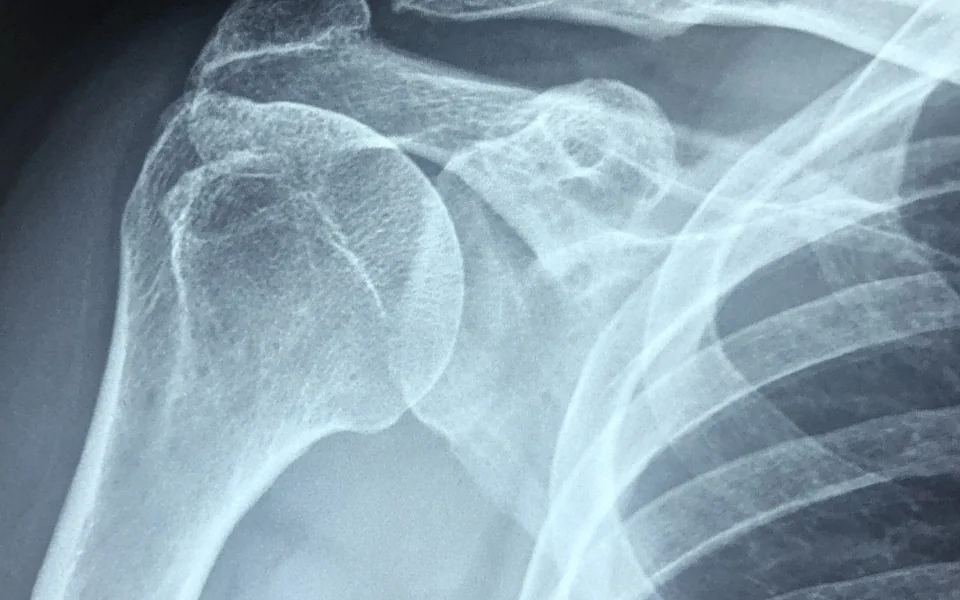

회전근개파열을 진단하기 위해서는 우선 전문의와의 상담을 통해 상세한 문진과 신체검사를 진행합니다. 이어서 X-ray, MRI, 초음파 검사 등을 통해 손상의 정도를 확인하게 됩니다. 이러한 진단 방법을 통해 회전근개파열이 확진되면, 그에 따른 치료 방법을 결정합니다. 각 검사 방법은 서로 다른 정보를 제공하며, 복합적으로 사용하여 정확한 진단을 내리는 것이 중요합니다.